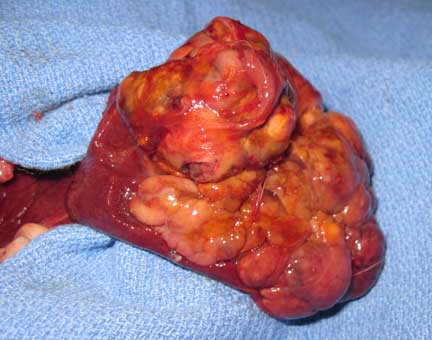

This liver lobe that is filled with cancer has been exteriorized from the abdomen and is laying on a surgical drape. Not the healthy liver lobe on the left part of this cancer filled liver lobe.

This lobe of cancerous liver in the surgeons hands just before removing it

The other liver lobes (you can see the cancerous lobe at the top left) are not healthy. They have nodules in them that are probably from the spread of the cancer from the cancerous liver lobe at the top left. A liver in this condition is a poor prognosis.